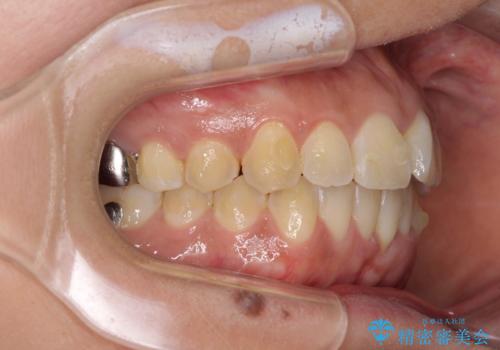

インビザラインによる狭窄歯列の拡大矯正

- 前歯のデコボコを治したいとのことで来院された患者様です。

上下顎ともに歯列全体の後方移動と側方拡大、IPR(歯と歯の間を削る)によってデコボコが解消するように設計し、インビザラインにより治療を行うこととしました。

後方移動に際し、上下の親知らずは4本とも抜歯することとしました。